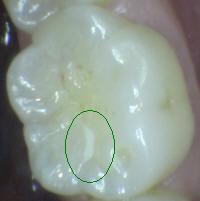

1 |

Sellador parcial |